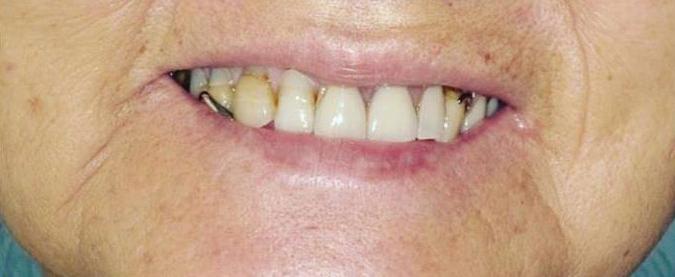

Increase Your Self-Confidence

A Beautiful Smile –Your Secret Weapon

Self-confidence and success have a symbiotic relationship; they exist in progress harmony. Perception is reality – the more self confidence you have, the more likely you are to succeed.

Developing Your Self-Confidence

Although many of the factors affect-

ing self-confidence are beyond your control, there are a number of things you can consciously do to build self-confidence.

A beautiful smile is one thing that you can control, and having a beautiful smile increases confidence and self-esteem. As your self-confidence builds you will feel better about yourself. When you feel better about yourself, other people will see you in a more positive light.

A beautiful smile makes you more attractive – smiling attracts people to you. Smiling more often changes your mood, and makes you look younger, hence you also feel younger.

What Makes a Smile Beautiful?

While not every person is born with a perfect smile, qualities such as straightness, cleanliness or whiteness of teeth may come to mind. Thanks to developments in the field of cosmetic dentistry,